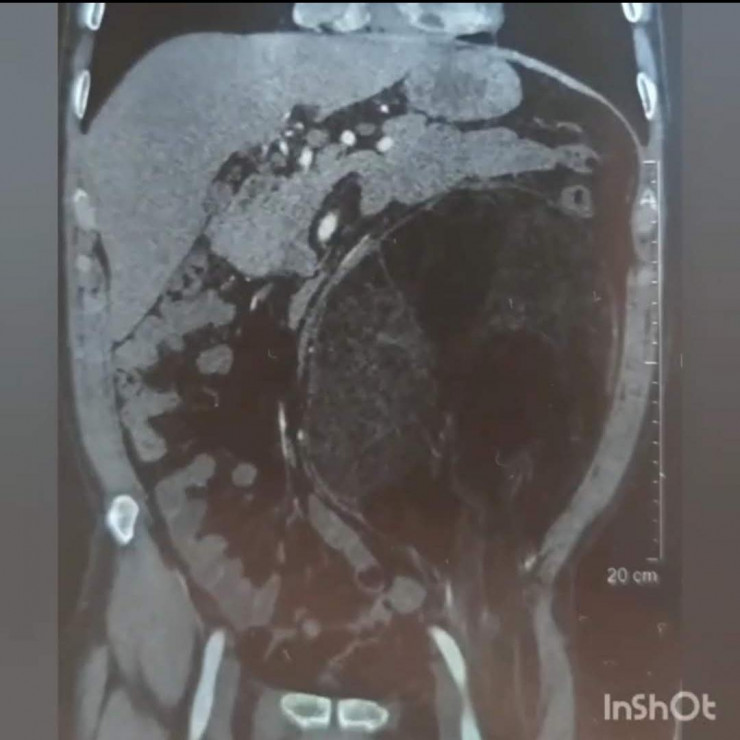

На КТ было обнаружено объемное образование. После тщательных анализов и обследований консилиум решил делать операцию по удалению образования.

Пациенту был выставлен диагноз – образование забрюшинного пространства с переходом в пахово-бедренную область слева.

На момент операции размер образования был 25-30 сантиметров, а вес образования составил 2,240 килограмма.

"Сложность операции заключалась в самом расположении образования. Оно сдвинуло все органы брюшной полости в одну сторону, разместившись на всей левой половине. Границы образования находились очень близко к аорте, образование практически лежало на аорте, прилегая к левой почке и мочеточнику, а внизу образование ушло через паховую область, проходя совсем рядом с бедренной артерией в верхнюю треть бедра. Сложность доступа заключалась в том, что нужно было сделать дополнительный разрез в паховой области. Чтобы извлечь образование, пришлось в три руки очень осторожно отделять образование от органов, к которым оно буквально приросло. Образование удалось извлечь, не нарушив целостности, что очень важно", - объяснил заведующий операционным блоком ГБСНП Нуркен Желдибаев.